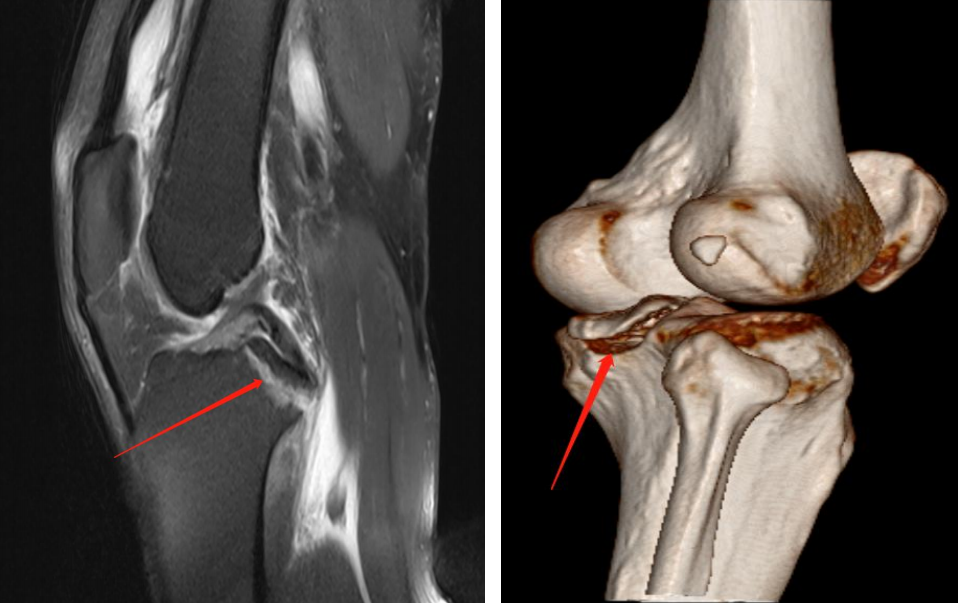

分型及术式

ⅢB型:多块撕脱骨折;合并半月板撕裂;BC>15mm;AE/AD≥1/2。

术式: 双袢(后叉前建立骨道)+骨道固定

合并内侧半月板放射裂

撕脱骨折、内侧半月板放射裂

半月板骨道固定、双袢固定撕脱骨折

术后X线片